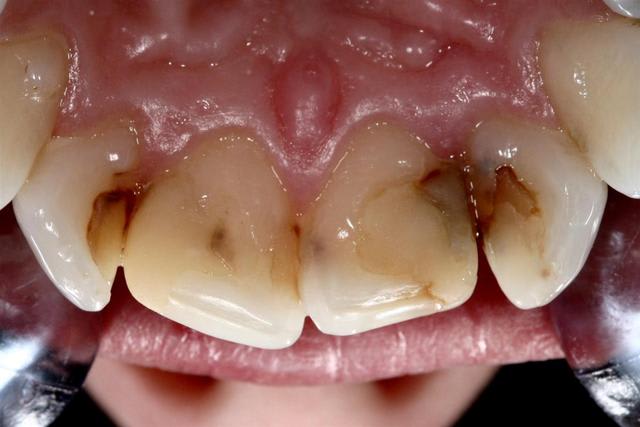

Reste un peu de colle :)

Il y a eu blanchiment

Pour info les compo avaient des vis intra dentinaire.. Encore un qui croyait pas dans le collage..

non, en plus là j'ai fait un petit alignement des collets des centrales... donc différé de 15 jours...

La patiente n'est pas fumeuse...la gencive est parfaitement saine. L'empreinte est un jeu d'enfant.

Pour les cas esthétique comme cela il vaut mieux prendre son temps...